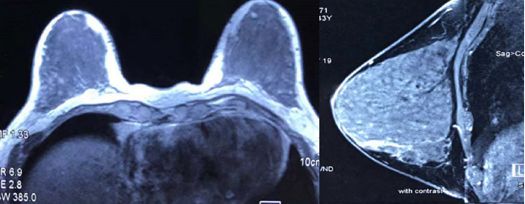

患者入院后查体:双侧乳房对称,双侧乳头无内陷,无异常分泌物,表面皮肤无红肿,右侧乳腺外下象限可触及一3cm×3cm大小包块(约7点方向,距乳头约5cm),无压痛,质地硬,边界不清,活动度差,与胸壁粘连固定,右侧腋窝可触及肿大淋巴结,左侧乳腺及左腋下未触及异常。相关影像学和实验室检查示:①乳腺超声:右侧乳腺8点方向距乳头约5cm可见大小约2.9cm×1.6cm×2.5cm低回声,边缘不清,形态不规则,内可见丰富血流信号,BI-RADS 4类。右侧腋窝可见肿大淋巴结,皮髓质界限不清。②乳腺MRI(图1)示:右乳外下象限胸壁前方见一个不规则团块状稍长T2信号,周围环绕片状长T2信号,TIC呈流出型,大小约2.6 cm×2.6 cm×2.9cm,BI-RADS 4类,肿块后缘与右侧胸壁界限不清。③超声心动示:左房、左室大,左室舒张、收缩功能减低,二尖瓣返流(中-重度),双平面法估测EF:32%。④脑利钠肽(brain natriuretic peptide,BNP)2132pg/L。④余胸部CT、腹部B超、骨扫描、血肿瘤标志物等检查未见明显异常。

图1 乳腺MRI(入院后)